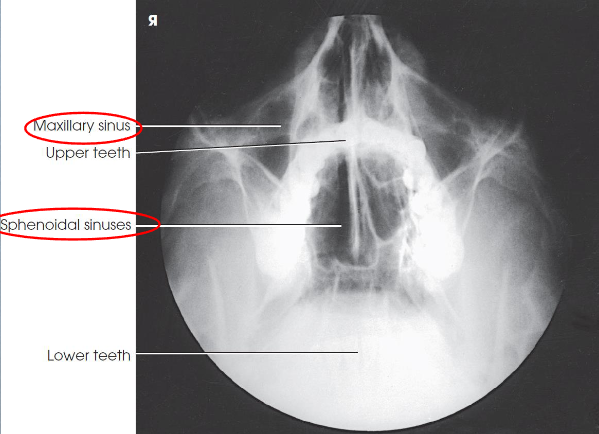

Parietoacanthial (open-mouth Waters) sinuses

patient position:

upright

MSP centered to midline

part position:

rest chin on IR

hyperextend neck to place OML at 37 degree angle from IR

MSP perpendicular to IR

open mouth

respiration suspended

CR:

horizontal, exits acanthion

collimation:

1 inch beyond the lateral skin shadows, superiorly to include just the shadow of the top of the head, and inferiorly to the occlusal plane

Parietoacanthial (open-mouth Waters) sinuses image criteria

demonstrates:

sphenoid sinuses through open mouth

maxillary sinuses

petrous pyramids lying inferior to maxillary floor

(OML in proper position)

no rotation or tilt

equidistant lateral borders of skull to lateral border of the orbits

summetric orbits and maxillary sinuses

MSP of head aligned with long axis of collimated field

air-fluid levels, if present